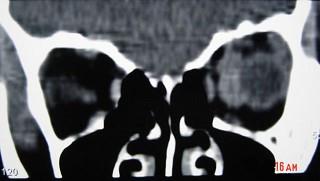

眼眶血管瘤(如图)的常见表现 ( )A、突眼B、搏动感C、疼痛D、眼球运动障碍E、视力障碍

问题 眼眶血管瘤(如图)的常见表现 ( )

选项 A、突眼 B、搏动感 C、疼痛 D、眼球运动障碍 E、视力障碍

答案 AB